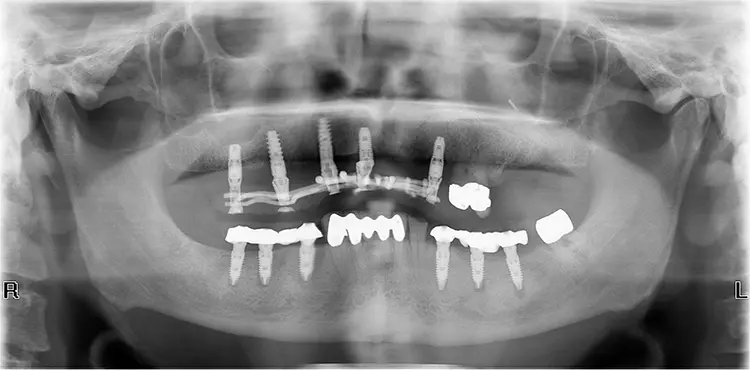

Die Ausgangssituation in diesem Patientenfall zeigte eine durch Abrasion/Erosion kompromittierte Ober- und Unterkieferbezahnung mit Distalbisslage und Labialstand der oberen Front (Angle-Klasse II/1). Des Weiteren zeigten sich Defizite im Weichgewebe. Es lagen generalisiert massive Rezessionen mit Miller-Klasse III bzw. Rezessionstyp 2 [6] v.a. im Ober- und Unterkiefereckzahnbereich vor.